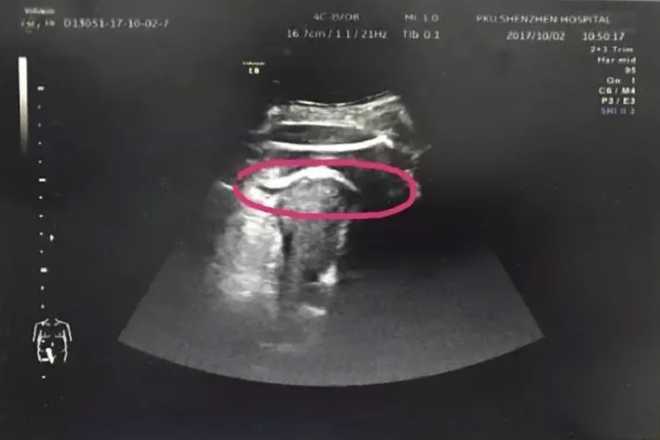

Peking University Shenzhen Hospital​​

The hospital posted a picture of the woman’s ultrasound on social media.